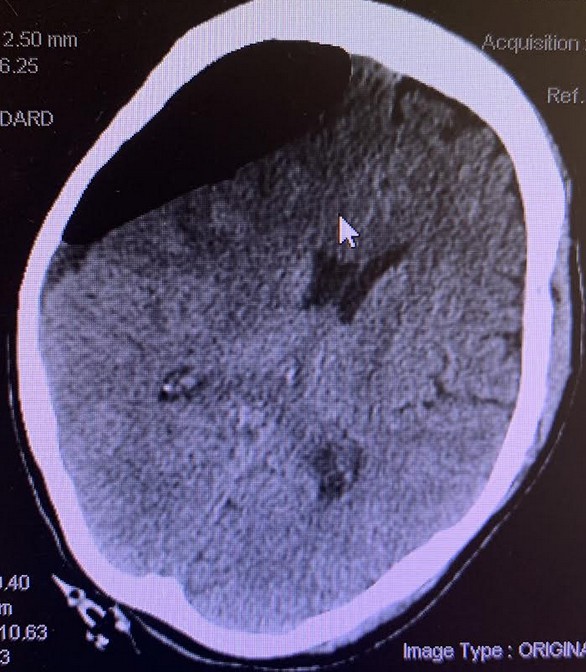

On Postop day 15, the patient was returned to the hospital for weakness and decreased appetite since discharge. On exam, patient was lethargic, followed commands intermittently, pupils equal round reactive to light (PERRL), left facial droop and left sided weakness 4/5. The patient was again found to have sinus tachycardia. The patient repeat CTH revealed resolution of the previously seen pneumocephalus, new interhemispheric SDH, previous bilateral subdural fluids collection increased right-sided subdural collection measures 16 mm in thickness compared to 11 mm previously and the left-sided subdural collection measures 11 mm compared to 5 to 6 mm previously, with increased midline shift to 6 mm (Figure 4).

Figure 4. CTH - Resolution of the previously seen pneumocephalus, a large bilateral subdural hemorrhage more prominent on the right than the left